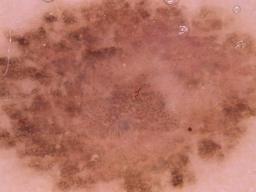

{

"age_approx": 35,

"anatom_site_general": "anterior torso",

"concomitant_biopsy": true,

"diagnosis_1": "Benign",

"diagnosis_2": "Benign melanocytic proliferations",

"diagnosis_3": "Nevus",

"diagnosis_confirm_type": "histopathology",

"image_type": "dermoscopic",

"lesion_id": "IL_6472749",

"melanocytic": true,

"sex": "female"